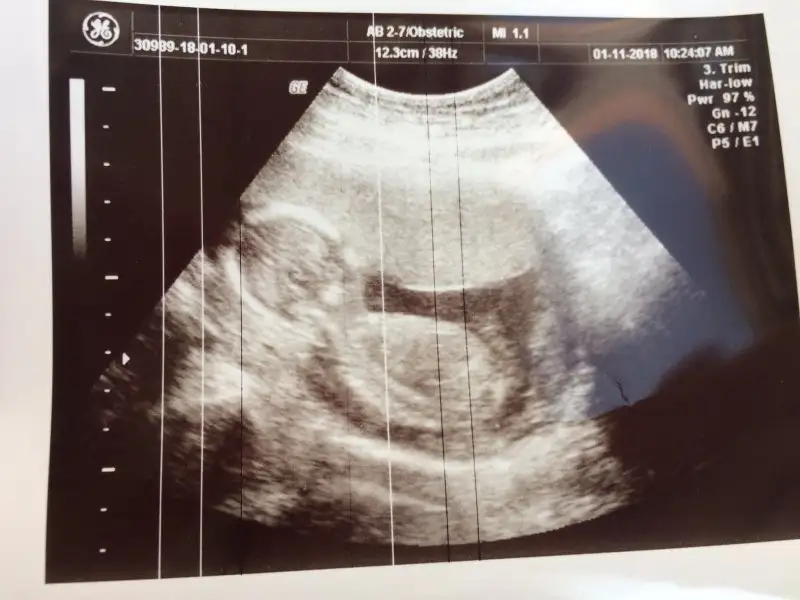

Teyzeleri bu da benim kızımın bugünki resmi netleşti artık cinsiyeti KIZIM oluyor inşallah 128 gr baştan popoya 9cm dedi göbekli tospiğim ya hayırlısıyla bebişlerimiz bi doğsaydı çok merak ediyorum kime benziyor diye Allahım bu duyguları tatmak isteyen herkese nasip etsin inşallah

• 077E6DEC-01DC-44F0-8F84-8EA9130217F5.webp

24,3 KB · Görüntüleme: 104